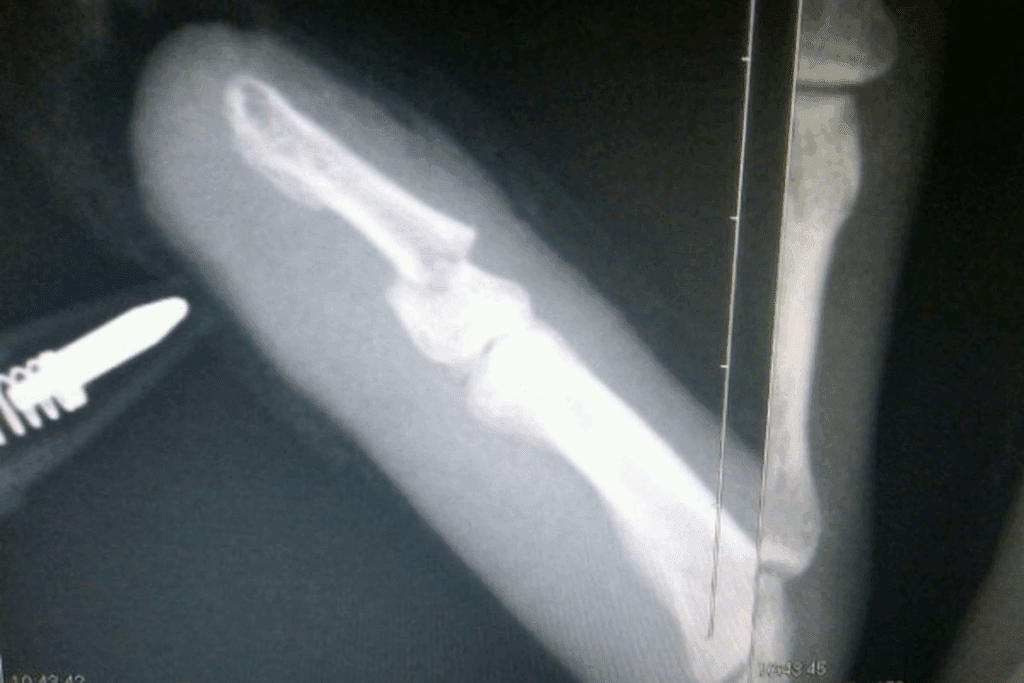

X-Ray Confirmation

X-rays are often used to confirm a finger fracture. They show the bone’s structure clearly. This helps doctors see where and how bad the fracture is. X-ray confirmation is essential for figuring out the fracture type and treatment.